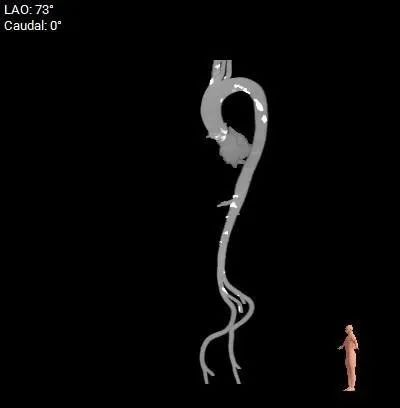

主动脉弓测量

主动脉弓部宽度、角度可

外周入路

腹主-双侧髂总动脉有少量钙化,股-髂动脉走行、内径可

• 拟主动脉瓣水平夹角约42°,非横位心,主动脉弓宽度角度可

• 腹主-双侧髂总动脉有少量钙化,股-髂动脉走行、内径可。